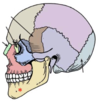

Clavicle

11

Q

A

Ulna

12

Q

A

Acromioclavicular Joint

13

Q

A

Radius